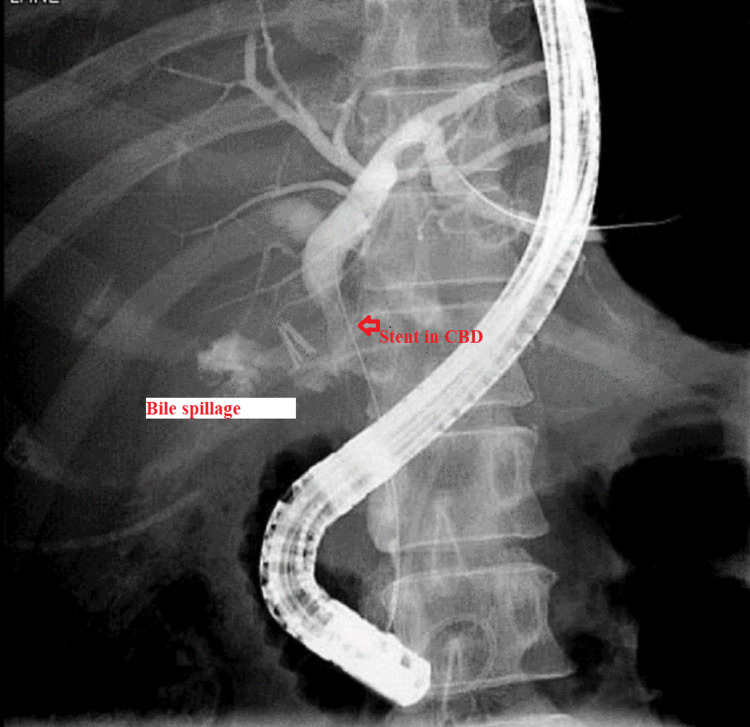

The patient was maintained on supportive treatment and close observation and was planned for endoscopic retrograde cholangiopancreatography (ERCP) and stenting. It showed a filling defect at the most distal part of CBD. Deep cannulation of CBD was achieved. A contrast leak was detected from the cystic stump with normal intra- and extrahepatic bile ducts. A partial sphincterotomy was performed, and a double pigtail stent was placed at the left hepatic duct, which eventually showed good contrast and bile drainage into the duodenum documented endoscopically and fluoroscopically (Figures 6, 7).